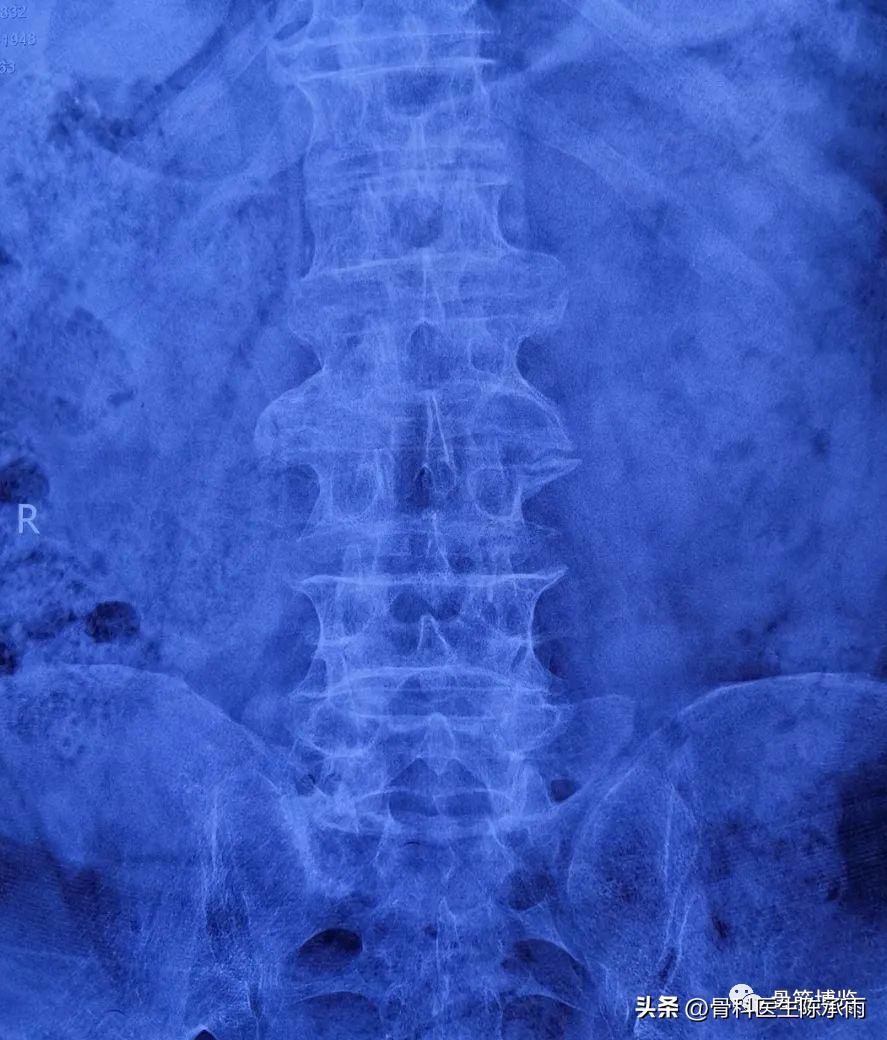

2例 多个间隙狭窄,以腰3/4和4/5为重

术前影像